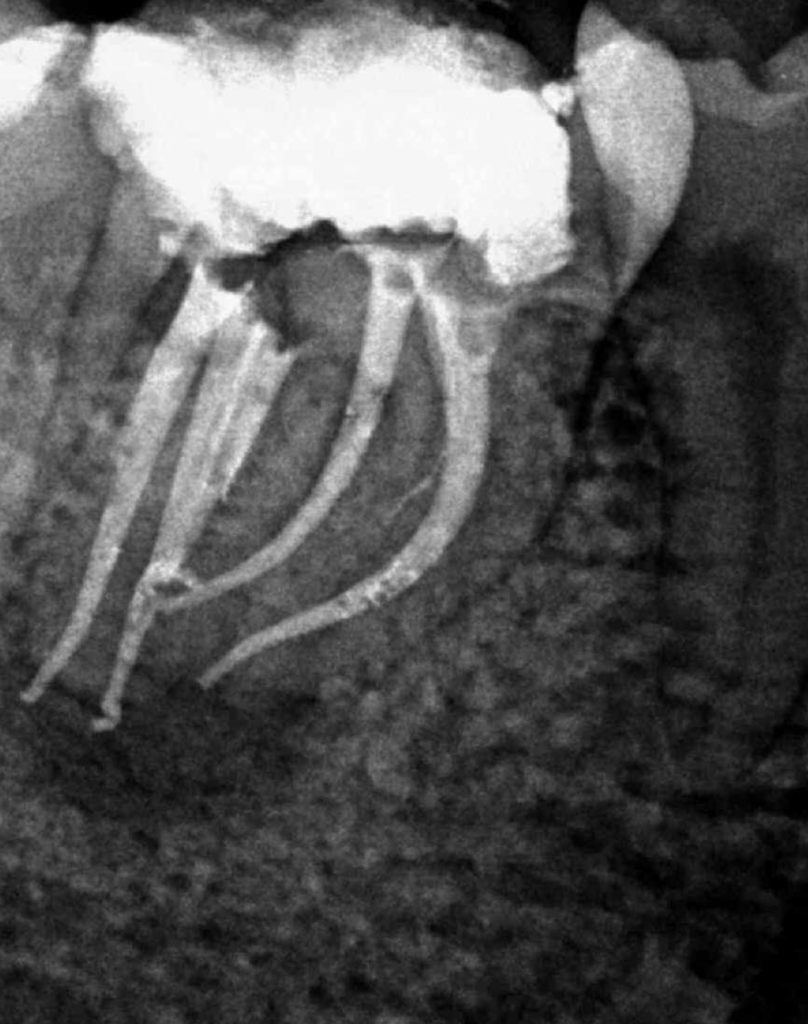

Molar gran curvatura bifurcación palatino